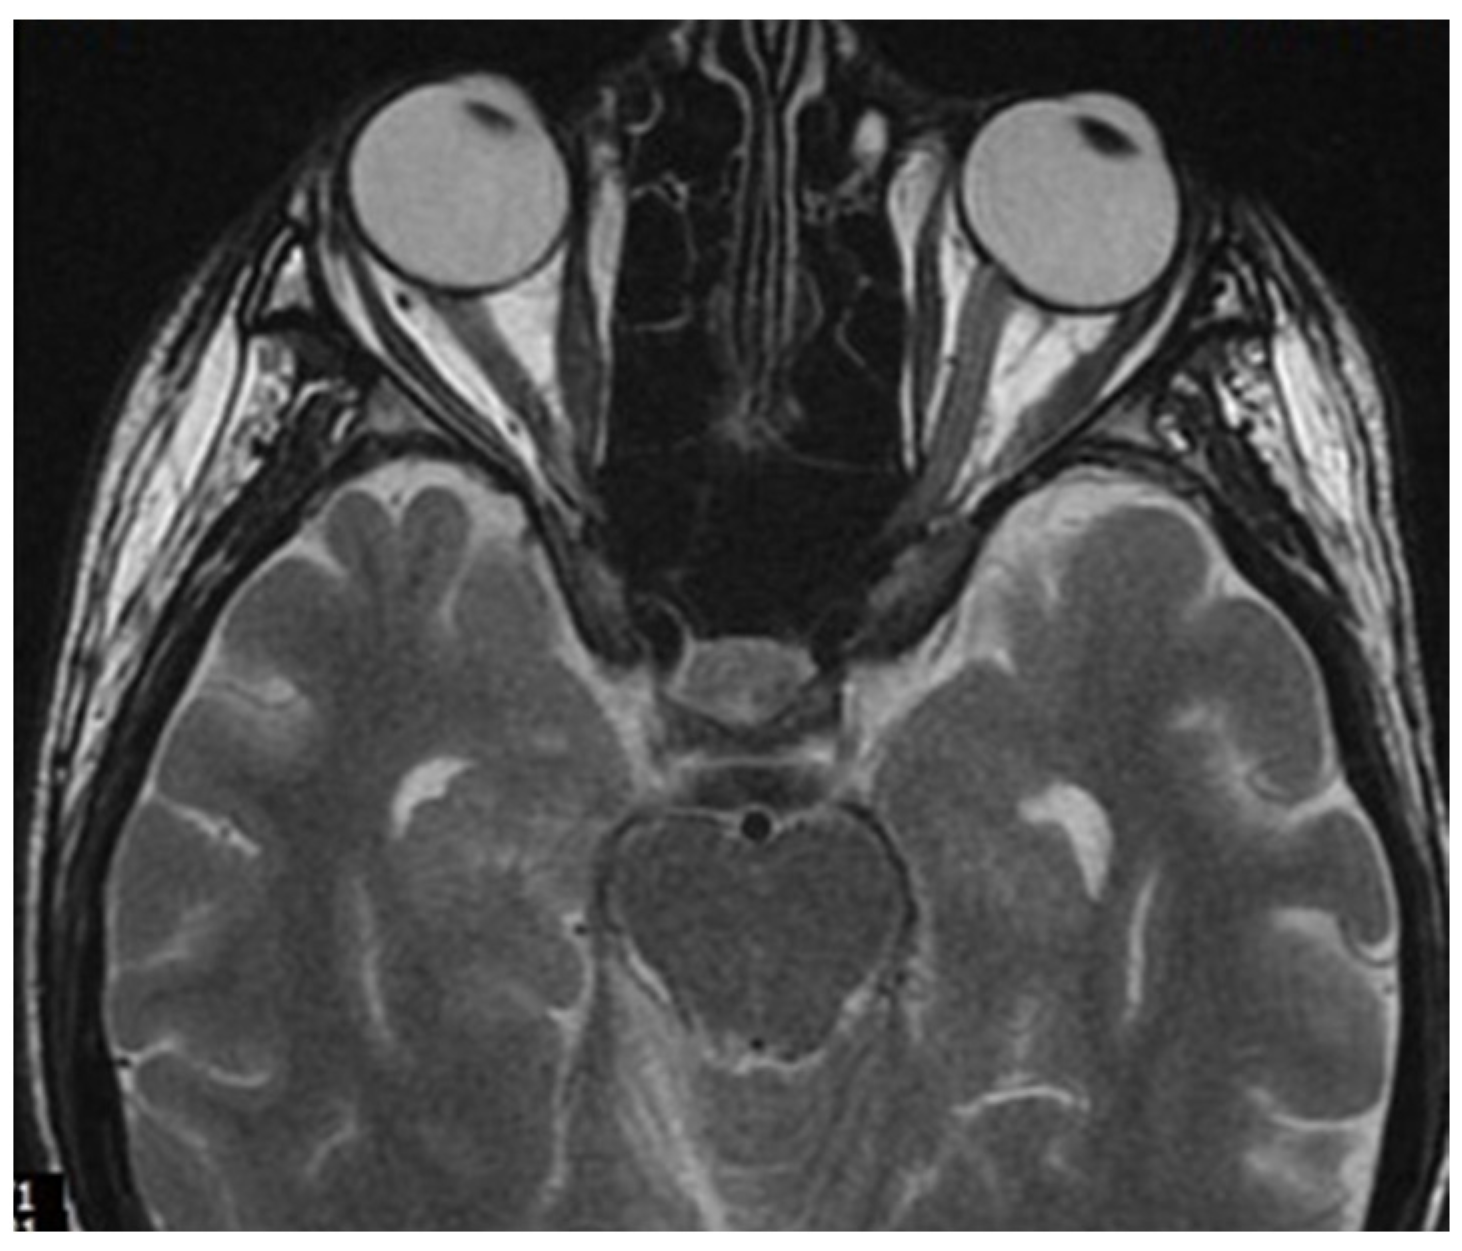

2. Case Report